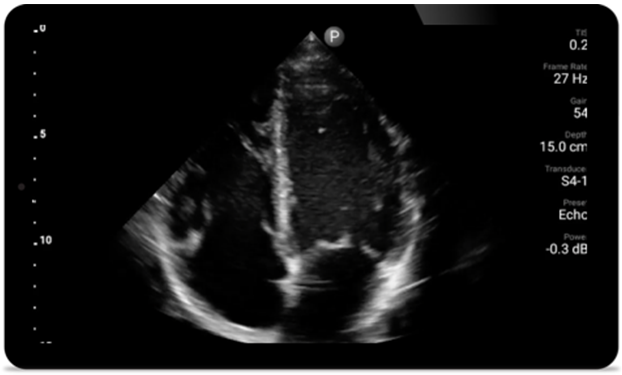

Every second counts in cardiac care

Heart attack patients need immediate care. Lumify's cardiac presets can help patients get diagnosed faster to improve their outcomes.